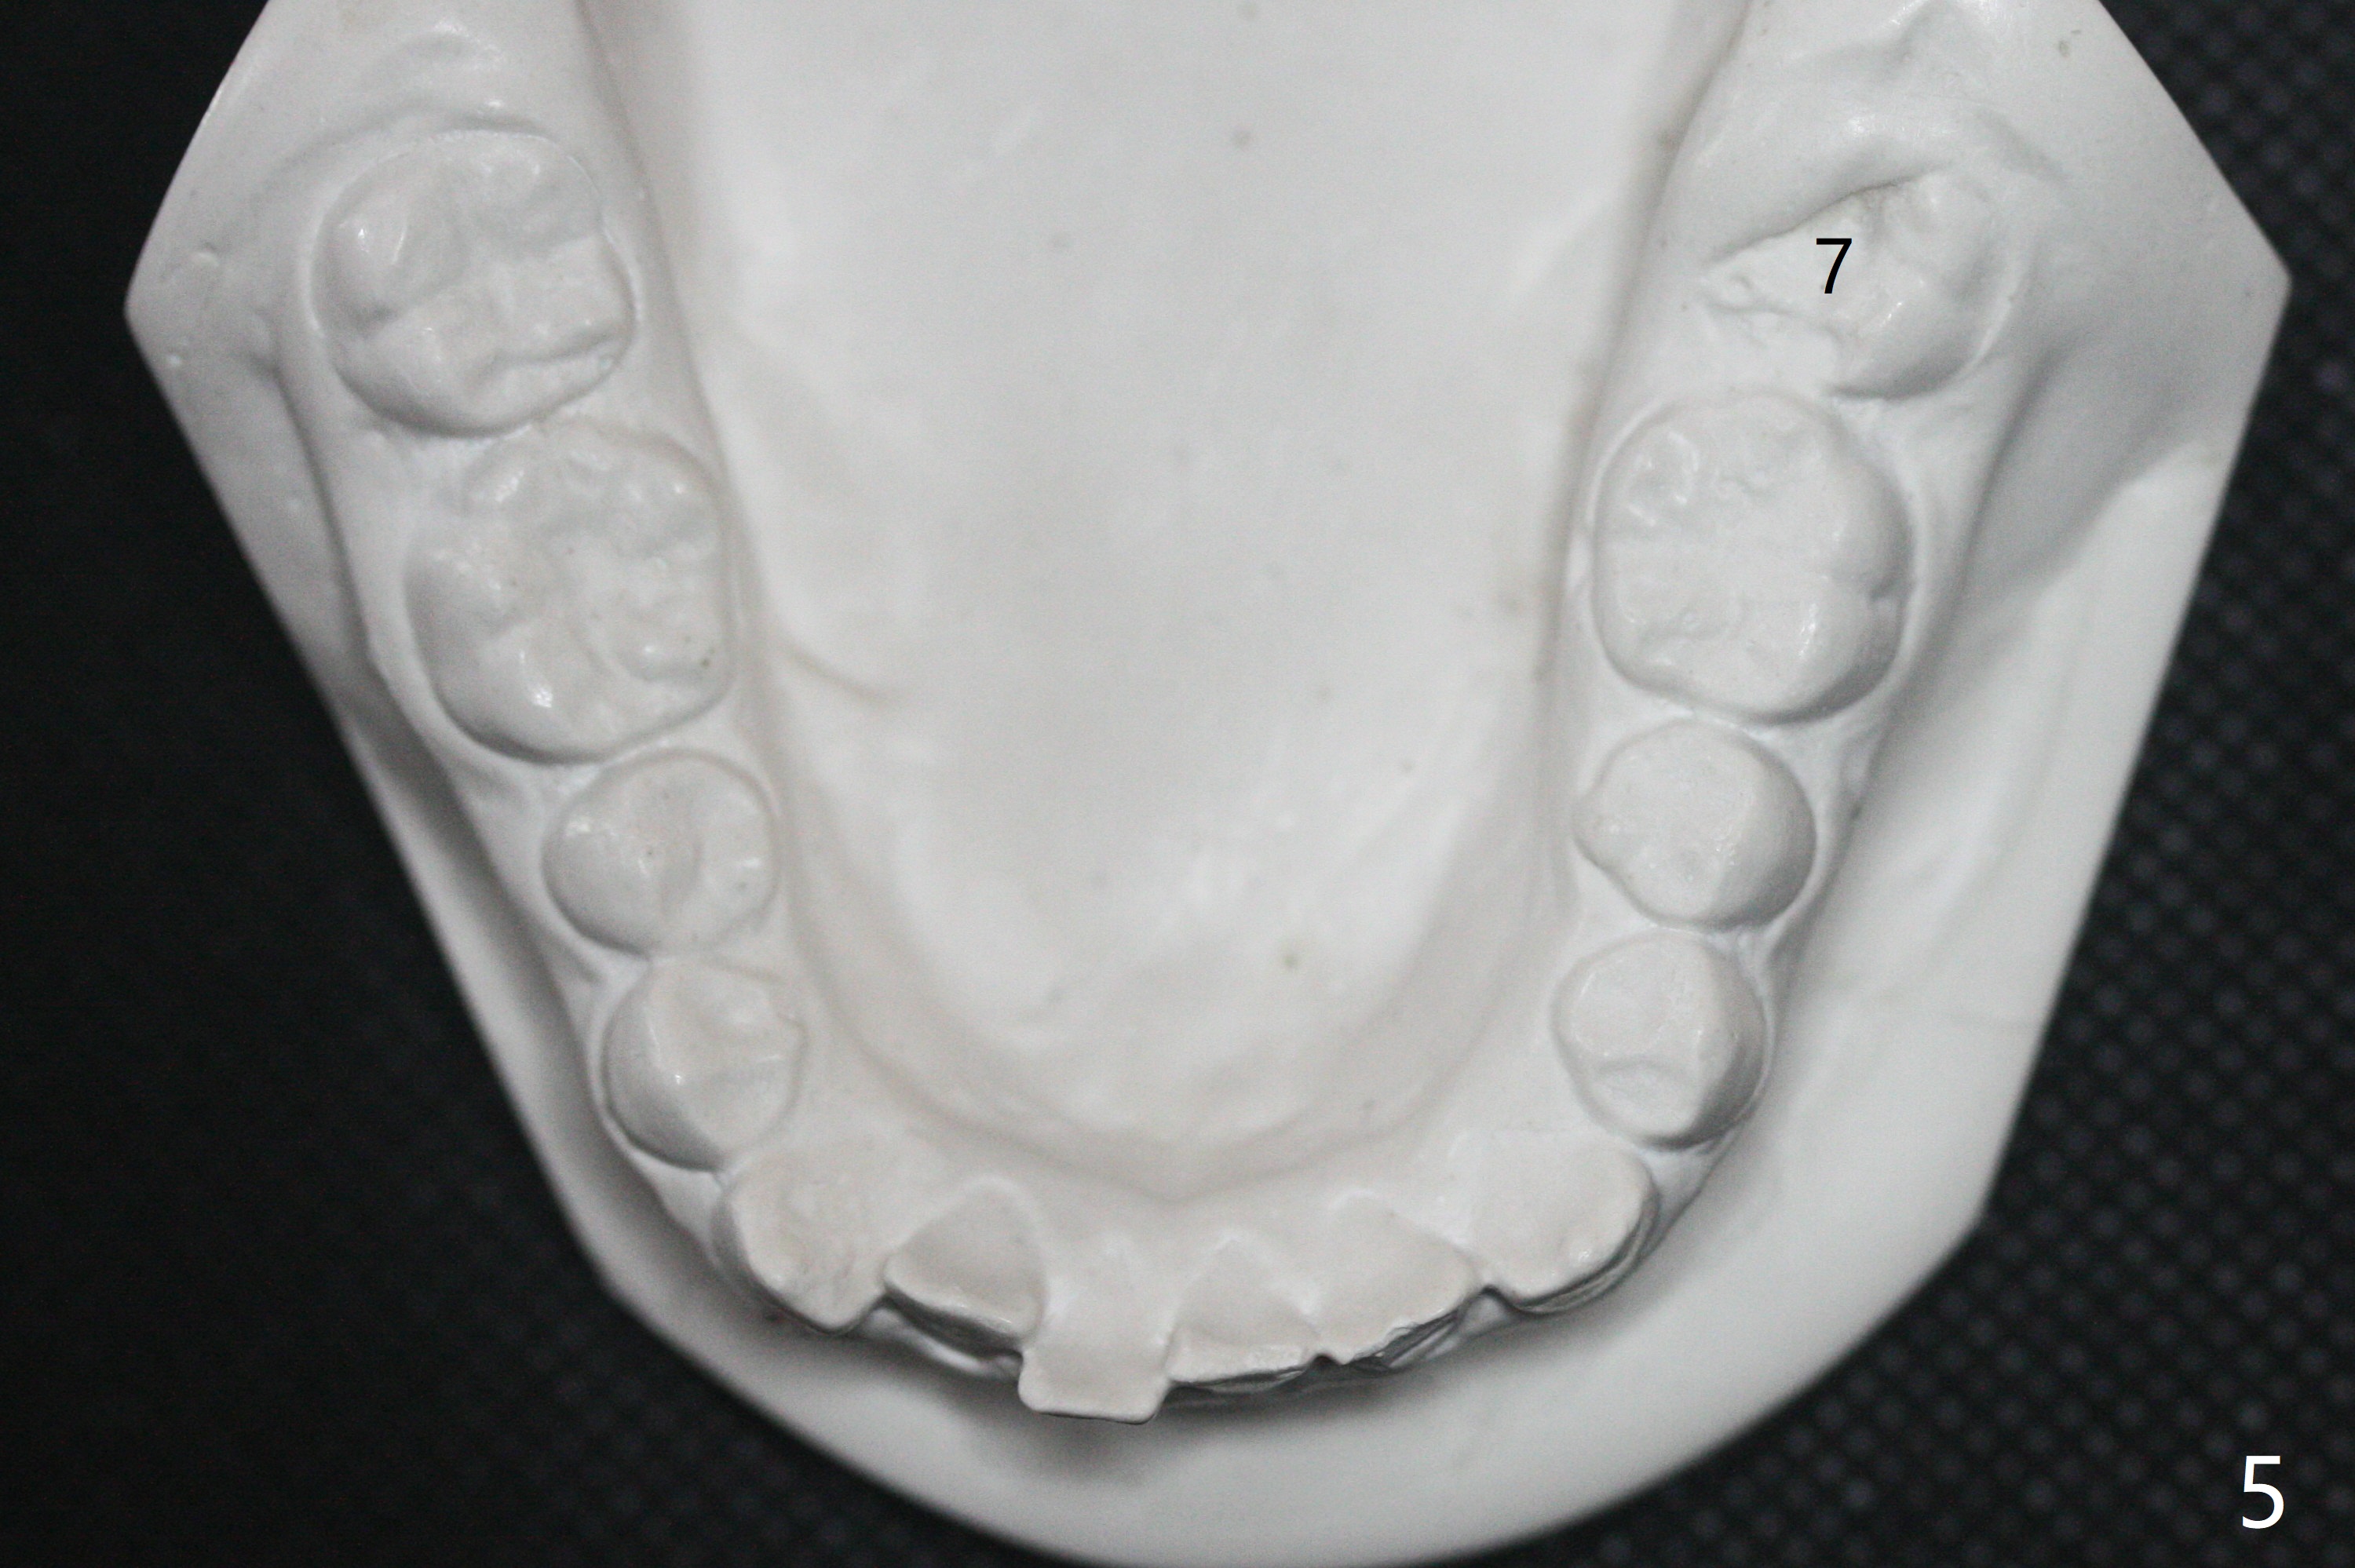

A 12-year-old woman has severe crowding including UL7 impaction (Fig.1-5), finishes non-extraction orthodontics at the age of 15 (Fig.1'-5') and returns for retainer remake at 19 (Fig.1''-5''). Four years post debanding, UL7 (Fig.4') seems to improve its position (Fig.4'').